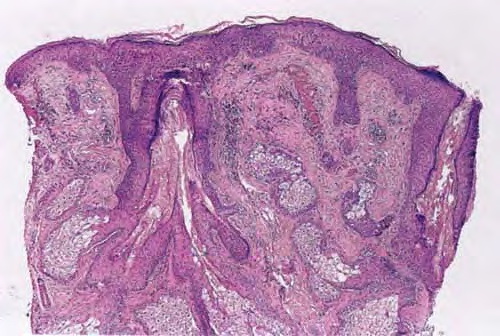

Rheumatoid neutrophilic dermatosis = الجلاد بالمعتدلات الرثواني RHEUMATOID ARTHRITIS Rheumatoid arthritis (RA) is a systemic inflammatory autoimmune disease that is characterized by a debilitating chronic, symmetric polyarthritis with significant extra-articular manifestations, which include rheumatoid nodules, pyoderma gangrenosum, granulomatous dermatitis, vasculitis, and internal organ involvement. The disease process is often progressive, resulting in limitation of joint […]